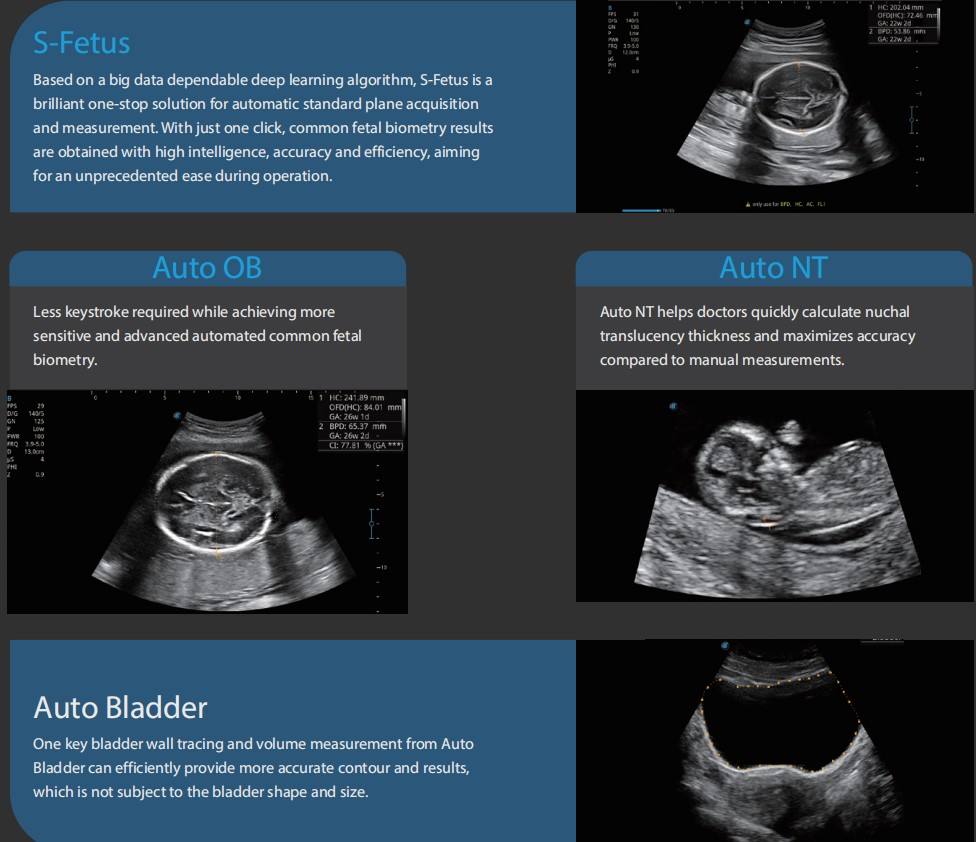

結構 超聲波

» 結構 性 超聲波 2d 3d 4d 分別 (99) 사진

結構 性 超聲波 2d 3d 4d 分別 (99) 사진